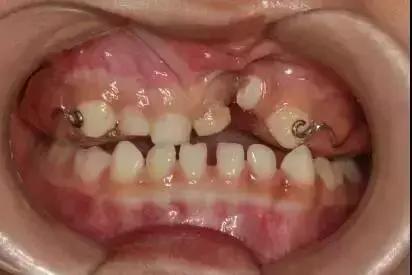

“孩子的牙齿长这样”, 怎么办?

没错,这就是俗称的牙齿“地包天”。

专业地说,儿童乳牙期“地包天”,就是乳下前牙咬合于乳上前牙唇侧,也叫乳前牙反颌,专业上属三类错颌。